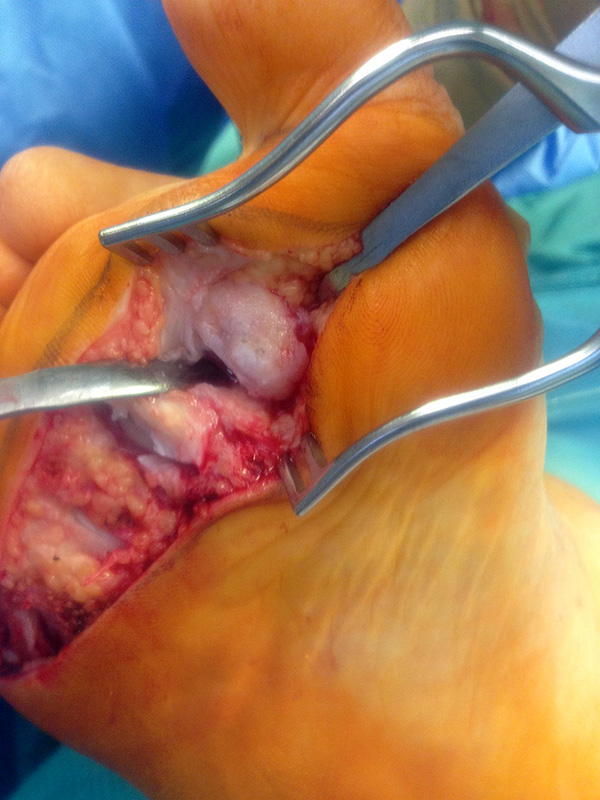

Die Operation nach Hoffmann-Tillmann (Abb. 4) ermöglicht durch die Resektion der Metatarsaleköpfe die Reposition der Zehen, da hierdurch der notwendige Platz geschaffen wird (Tillmann 1990). Meist sind nicht nur die knöchernen Strukturen der Metatarsaleköpfe destruiert, auch das plantare Polster ist disloziert, regelmäßig kommt es zur Ruptur der plantaren Platten mit Destruktion der Kapsel-, Band- und Sehnenstrukturen (Tillmann 2009) 6. Häufig findet man ausgeprägte Rheumaknoten oder Bursitiden plantar. Durch die breite, querovaläre Hautexzisionaus dem Vorfußballen werden plantare Schwielen entfernt, später beim Hautverschluß werden die plantaren Strukturen durch die plastische Dermatodese wieder in die Belastungszone reponiert.

Die Raffung des plantaren Kapselgewebes erfolgt mit 0er Vicryl. Besteht eine Lateraldeviation der Kleinzehen kann diese durch eine tibialseitige Raffung korrigiert werden. Tillmann beschreib in diesem Zusammenhang die Raffung der plantaren Gelenkkapsel tibialalseitig mit Einstich an der Grundgliedbasis und auf Höhe der metatarsalen Resektionsebene.

Das MTP V wird mittig gerafft zur Verhinderung eines Digitus quintus varus.

Das plantare Fettpolster wird in die Auftrittsfläche reponiert und mit Vicryl vernäht. Die plantare Hautnaht erfolgt mit robustem, nicht resorbierbarem Nahtmaterial (z.B. Ethilon 2,0).